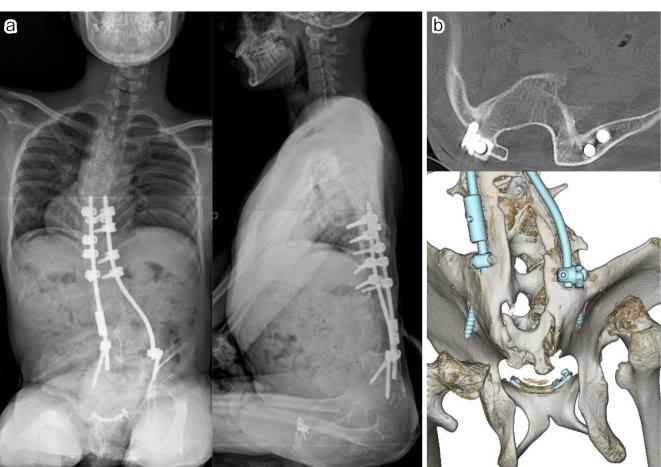

Case 1. A 10-year-old male underwent T8-S posterior fixation followed by multiple augmentations using allografts at the lumbosacral junction for delayed union. All additional procedures with bone graft using a posterior approach failed to achieve bone union; however, additional rigid fixation at the pubic symphysis resulted in a successful lumbosacral bone union. Case 2. A 6-year-old male underwent vertical expandable prosthetic titanium rib (VEPTR) surgery with multiple rod extension procedures. Subsequently, at the age of 10 years, a combined two-stage anterior (L1-3) and posterior (T8-iliac) fixation with T9 hemivertebrectomy was performed. As a result of subsequent nonunion with screw loosening, additional rigid fixation at the pubic symphysis was performed 1 month after posterior fixation. Bone union was finally achieved 1 year after all the surgical interventions.

病例1。一名10岁男性接受了T8 - S后路固定术,随后在腰骶部交界处使用同种异体骨进行了多次增强手术以促进延迟愈合。所有采用后路植骨的额外手术均未能实现骨愈合;然而,耻骨联合处的额外坚强固定导致腰骶部成功骨愈合。病例2。一名6岁男性接受了垂直可扩张人工钛肋骨(VEPTR)手术及多次棒延伸手术。随后,在10岁时进行了两阶段联合前路(L1 - 3)和后路(T8 - 髂骨)固定并进行了T9半椎体切除术。由于随后出现螺钉松动导致不愈合,后路固定术后1个月在耻骨联合处进行了额外的坚强固定。在所有手术干预1年后最终实现了骨愈合。